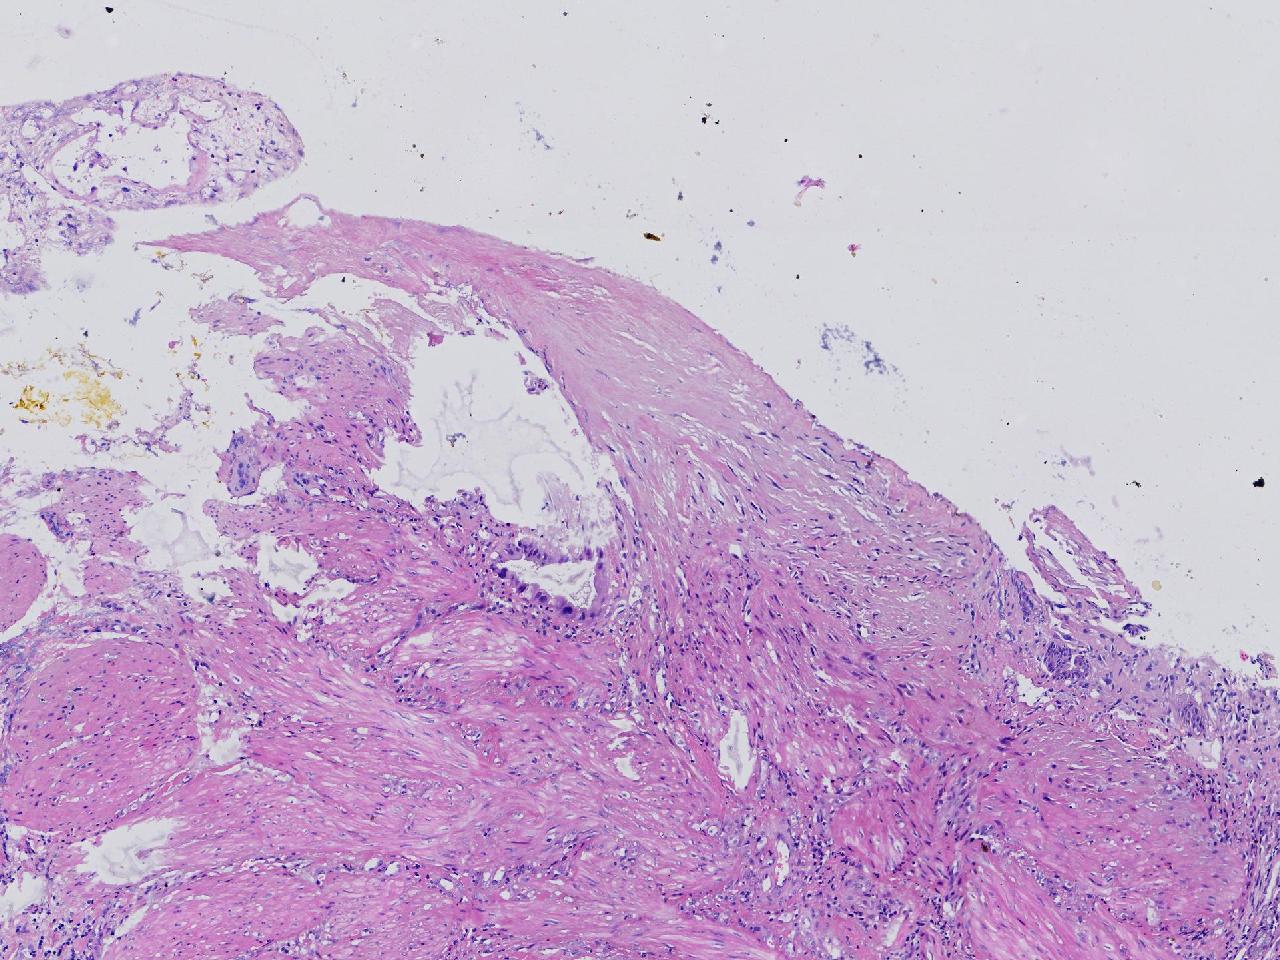

这些腺体有问题吗?

性别

女

年龄

38岁

临床诊断

胆囊结石伴慢性胆囊炎

一般病史

右上腹疼痛不适7年余,外科行胆囊切除。

标本名称

胆囊

大体所见

灰粉色胆囊一条,部分粘膜粗糙,腔内见泥沙样结石。

细胞有异型,标记看看

有异型,最好再补取几块。

这个蜡块重新制片,又多处取材制片,支持炎性反应性改变。 不支持肿瘤性。